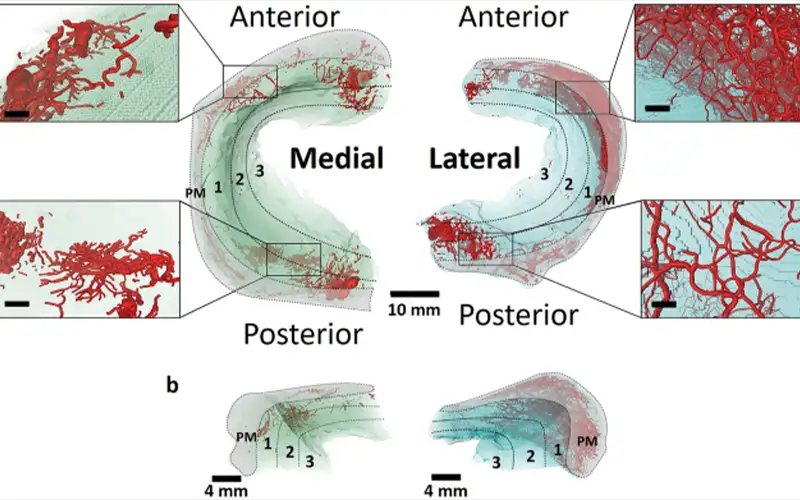

منیسکهای زانو از نظر خونرسانی به سه ناحیه اصلی تقسیم میشوند: ناحیه قرمز (Red Zone)، قرمز–سفید (Red-White Zone) و سفید (White Zone) که از حاشیه به سمت مرکز منیسک قرار دارند.

بهجز بخش محیطی منیسکها، سایر قسمتها فاقد عروق خونی هستند و تغذیه آنها از طریق انتشار مواد غذایی از مایع مفصلی انجام میشود. حدود ۱۰ تا ۳۰ درصد از حاشیه خارجی منیسک خارجی و ۱۰ تا ۲۵ درصد از حاشیه منیسک داخلی دارای عروق خونی هستند.

اعصاب منیسکها مسیر عروق را دنبال میکنند و بیشترین تراکم عصبی در نواحی شاخ قدامی و شاخ خلفی منیسکها دیده میشود که نقش مهمی در حس عمقی و درد زانو دارند.